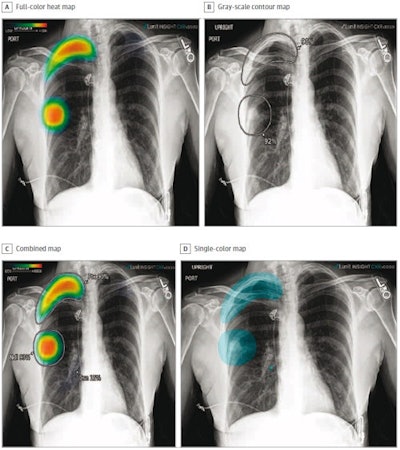

The different display modes of AI output: Shown are the color heat map (A), grayscale contour map (B), combined map (C), and single-color map (D). Image courtesy of JAMA Network Open.According to the findings, on its own, compared with the ground truth, the algorithm achieved detection rates of 82.5% for lung nodules (94 of 114 findings), 88.7% for pneumonia (173 of 195 findings), 87.2% for pleural effusions (130 of 149 findings), and 100% for pneumothoraces (80 of 80 findings).